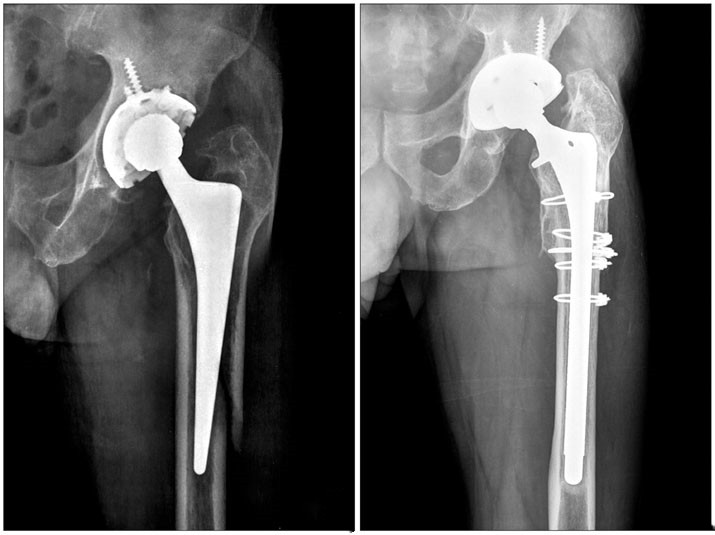

Выбор внутренней фиксации по сравнению с заменой сустава В настоящее время считается, что внутренняя фиксация полым стержнем при переломе шейки бедра имеет преимущества короткого времени операции, небольшой травмы и низкой стоимости, но у большинства пожилых пациентов наблюдается остеопороз, поэтому стабильность